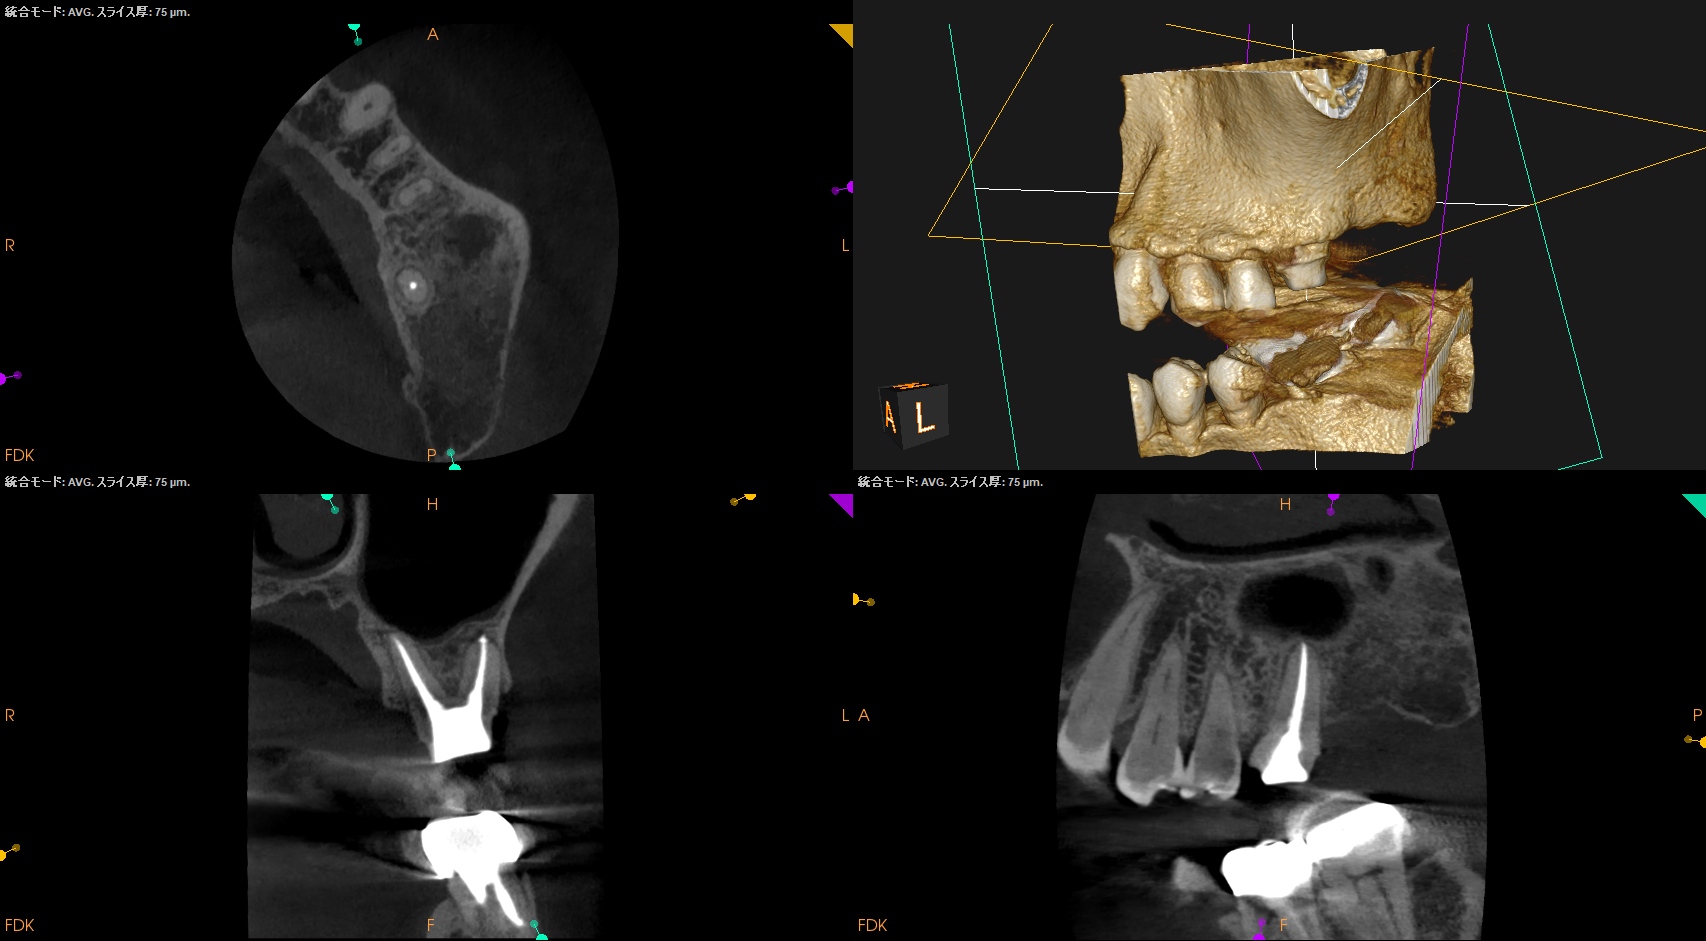

#14 RCT 2yr recall(2026.1.21)

MB1

MB2

DB

P

MB,DBの根尖部に病変が残存している。

臨床検査での咬合痛が生活に支障があるそうだ。